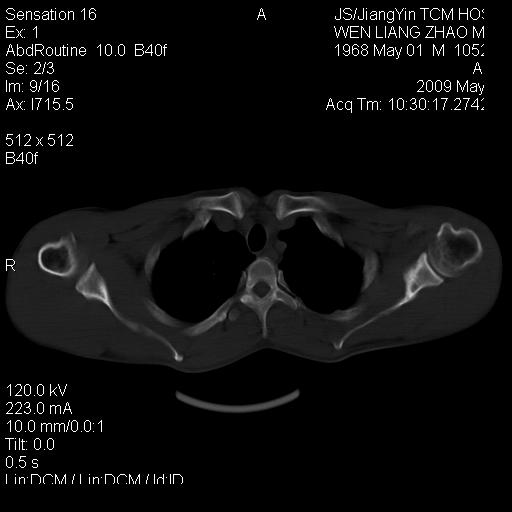

标题: CT19762:左侧喙突处压痛二年。考虑骨样骨瘤。 [打印本页]

标题: CT19762:左侧喙突处压痛二年。考虑骨样骨瘤。

左侧喙突处压痛二年。考虑骨样骨瘤。

病灶外缘膨胀明显,灶缘硬化较少,结合病史较符合骨母细胞瘤,其他亦不排除如软骨及软骨母细胞瘤等(病灶形态,成份较符合,发病部位也符合,只是年龄较大),骨样骨瘤多有较明显的自发性痛,且夜间痛明显,病史为压痛两年,不太符合.

多考虑内生性软骨瘤。年龄及发病部位及病史不支持骨样骨瘤。

支持骨样骨瘤(瘤巢小于1.5mm),骨母细胞瘤又称为巨大骨样骨瘤指瘤巢大于2cm的骨样骨瘤.

首先考虑内生软骨瘤,其次才考虑骨样骨瘤。